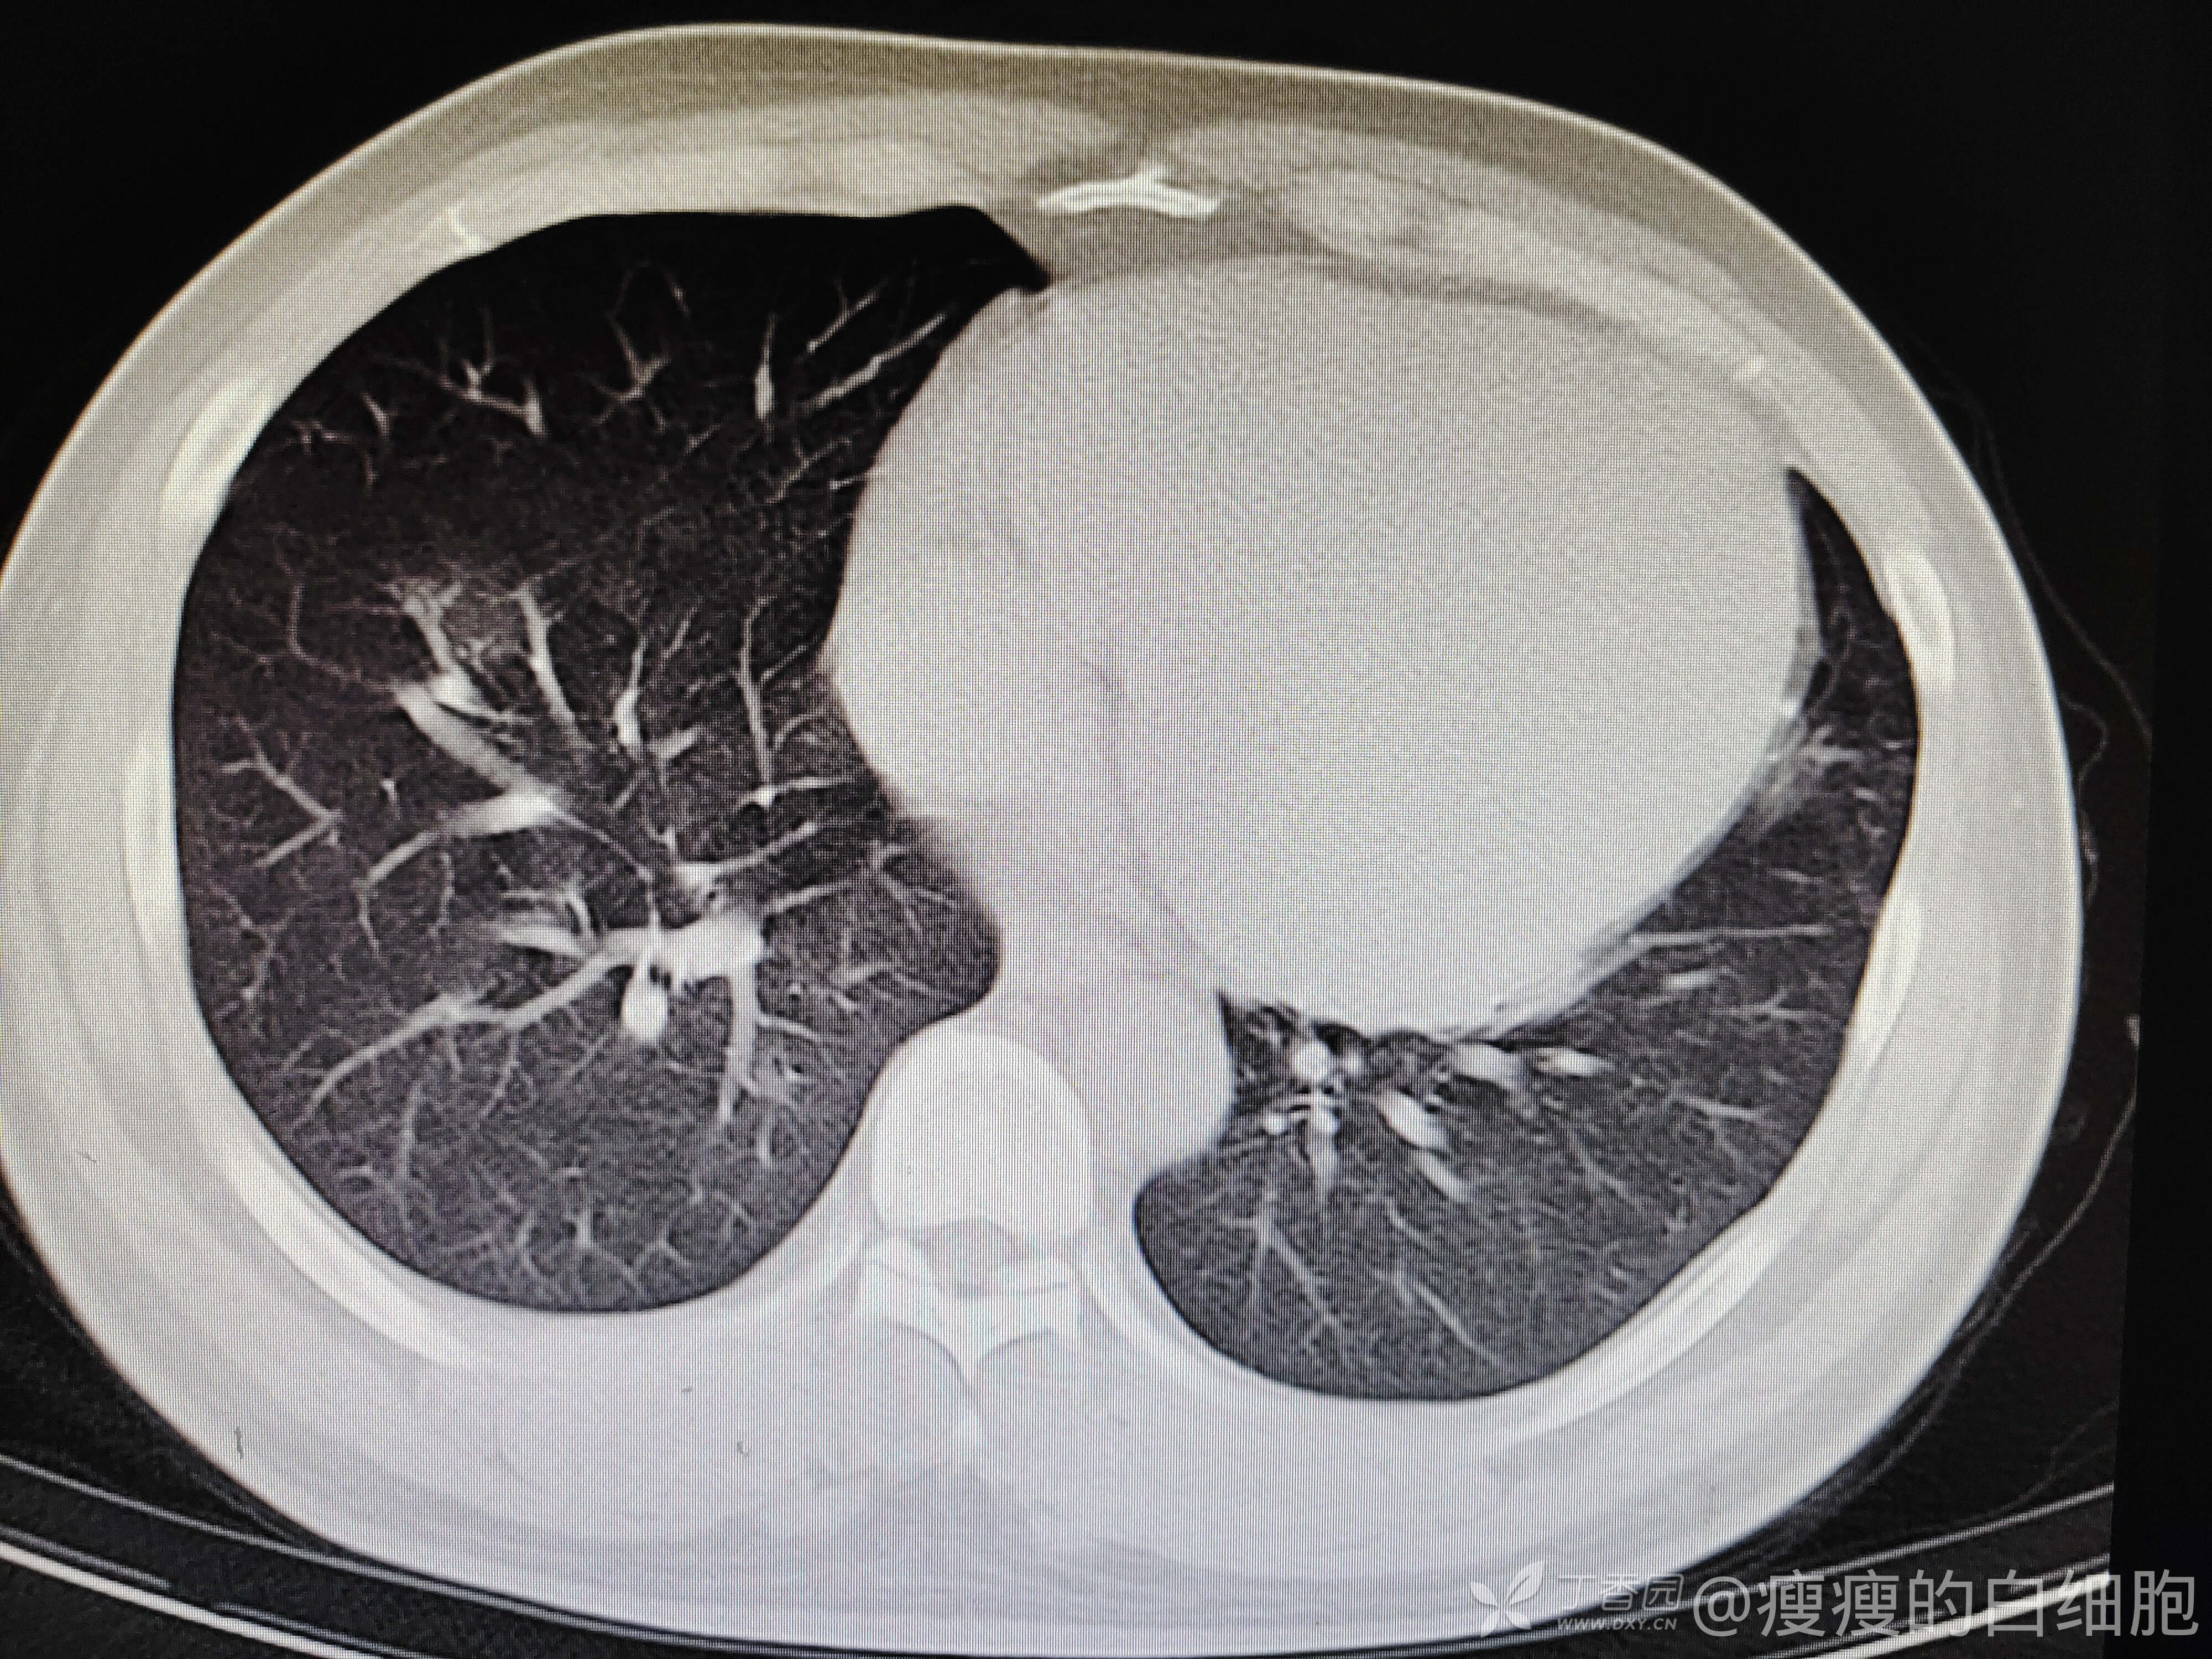

5天后咳嗽略减轻,但感胸闷。这时候血压达到了169/126mmhg,查体肺部无干湿性啰音,下肢也无水肿。再次复查胸部CT

新发病毒感染?还是心衰?继续完善检查,心电图大致正常。

好家伙,NT-pro-BNP这么高,心衰无疑了,给予降压、利尿、补钾等治疗后症状减轻,建议出院后继续口服利尿剂、抗生素后复查相关指标。